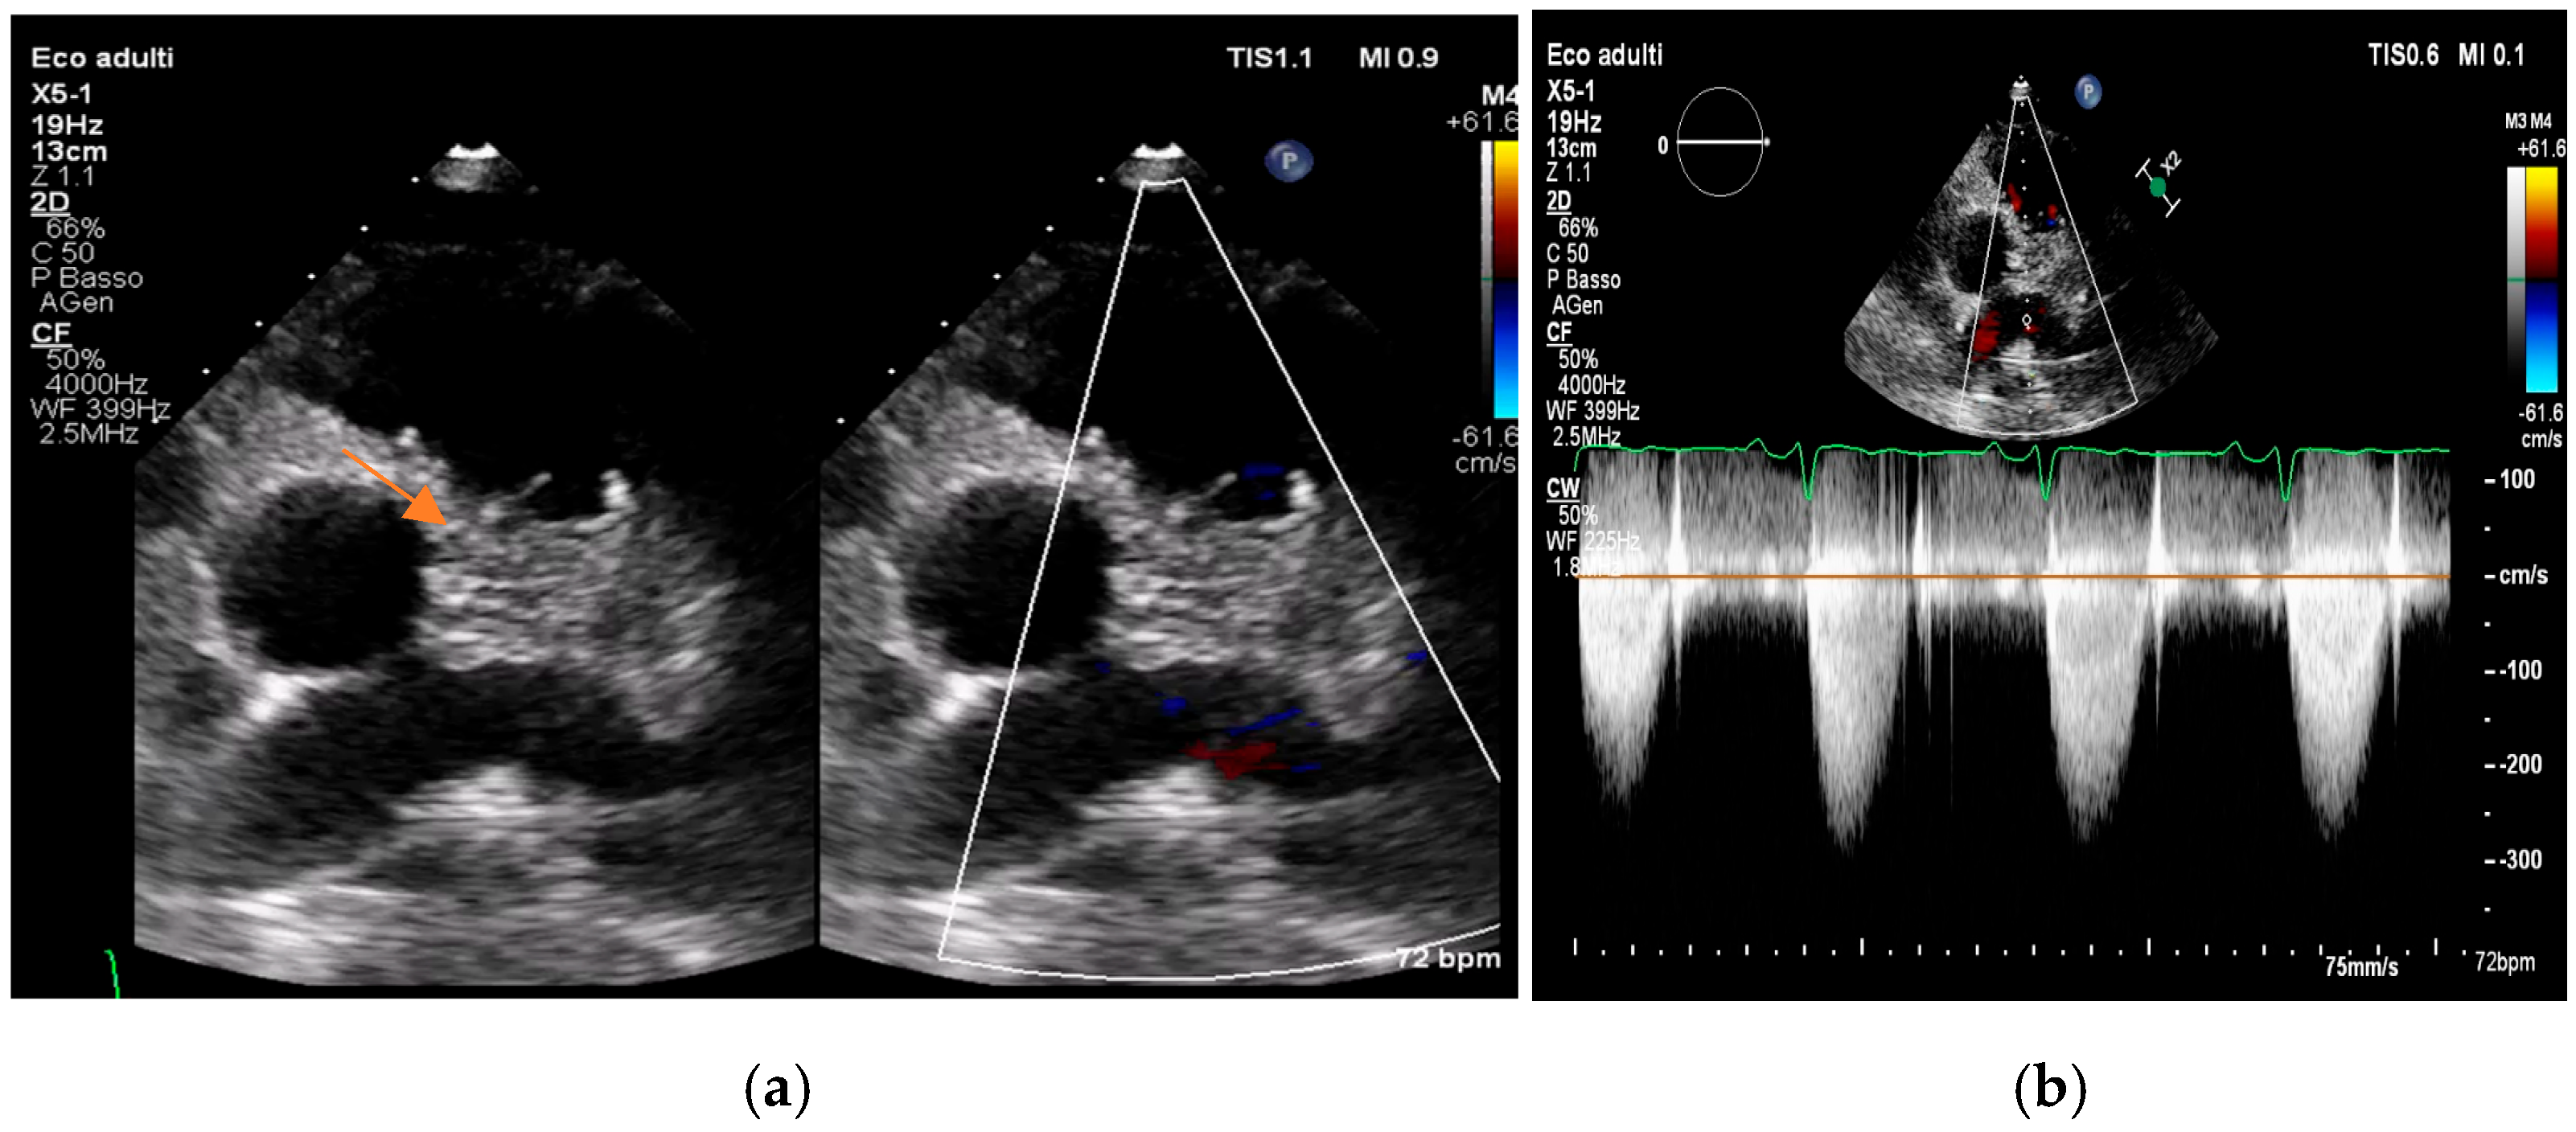

- pseudoaneurysm, a contrast-filled outpouching with a narrow neck communicating with the cardiac lumen, often adjacent to the valve annulus. On echocardiography, it appears as a pulsatile cavity with systolic expansion and diastolic collapse.

- intracardiac fistula, visualized as an abnormal communication between cardiac chambers or vessels, is often detected by using color Doppler.

- significant new valvular regurgitation compared with previous imaging, i.e., increase in regurgitant jet size, vena contracta width…